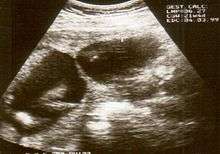

The diagnosis of constriction ring syndrome can be confirmed with an ultrasonography. The clinical manifestations can be extremely variable. It could be a single or multiple manifestation. This can be confirmed at the end of the first trimester or at the beginning of the second trimester.[9] But not every patient will be diagnosed at that moment, most will get this diagnosis at birth.